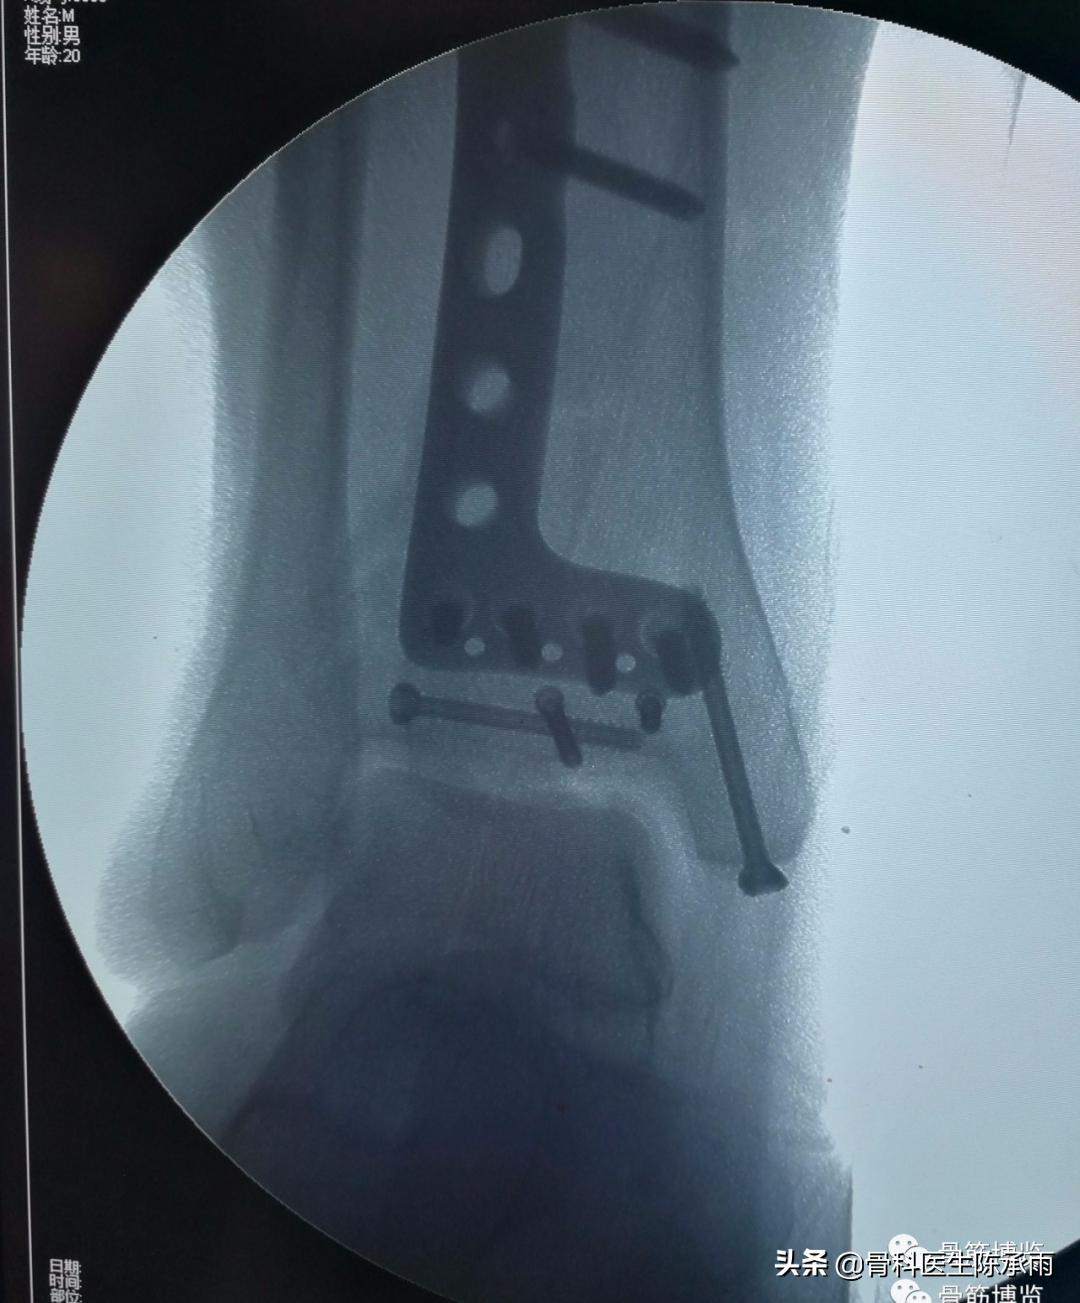

今天下午一台踝关节手术 ,内踝、前踝、后踝和腓骨下段骨折,虽然多见,也做过很多同类和更复杂的,但次手术都有所收获,只求自己的手术技能精益求精。

6、前踝解剖板尽量靠近关节面,以起支撑固定作用。

8、腓骨骨折及后踝可于同一切口内进行。

9、后踝骨折于腓骨长短肌后肌间进入显露,最后进行,新鲜骨折在另外三踝复位的情况下大多已经自行复位。可以用空心钉或后踝板固定。

10、如遇胫腓联合分离,同时可以拉力固定。但一般要求3个月内取出。

骨折固定满意。